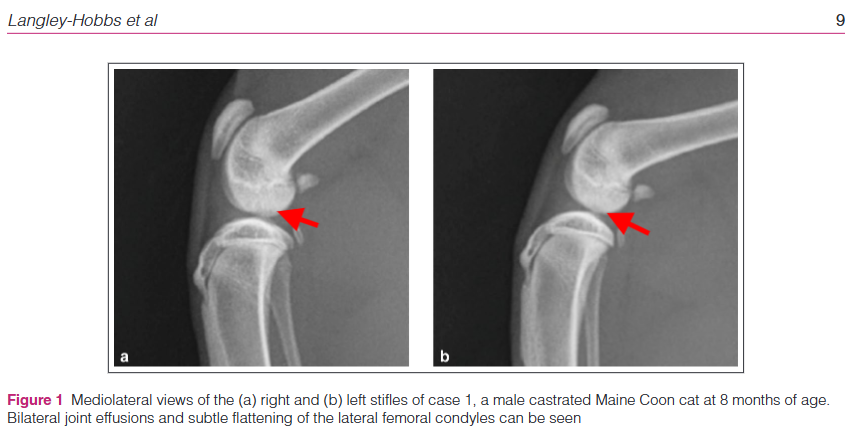

슬개골 연골 박리증은 X선 촬영, CT 촬영, 관절액 검사 등을 통해 진단할 수 있다. X선 촬영에서는 슬개골의 연골하골에 결손이 관찰될 수 있으며, CT 촬영에서는 보다 정확한 병변의 위치와 크기를 확인할 수 있다. 관절액 검사에서는 염증 세포의 증가가 나타날 수 있다.